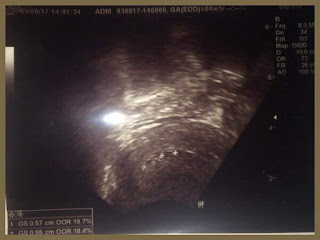

Finalmente fomos espreitar o que se estava a passar no útero.

"Ora cá está o saquinho... por acaso até tem dois saquinhos", disse a Dra. F.

Dois?? 😍 Olhei logo para o marido que sempre disse que adorava ter gémeos!

"O tamanho está compatível com o tempo de gestação, os contornos são regulares... parece estar tudo bem para já. Mas temos que ter calma. Temos que aguardar para ver se evoluem os dois. É muito comum haver 2 sacos gestacionais e depois só um deles evoluir."

No final deu-nos os parabéns e marcou nova consulta para daí a duas semanas.

Saímos da consulta radiantes! Dois saquinhos! Estava tudo bem!

Isso até eu ver na impressão da eco que um saquinho era claramente maior que outro. Pior! Comecei a ver medidas de sacos gestacionais pela internet e comecei a ficar muito insegura. E ía ter que aguentar duas semanas para ter novidades.